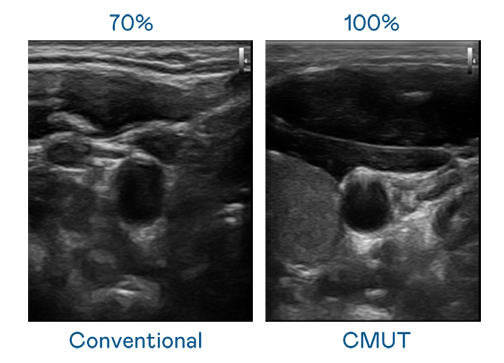

CMUT 技术是一种用电容式微机电元件来产生超音波讯号的技术。与传统 PZT 压电式技术相比,CMUT 频宽增加 30%,更宽频的超音波讯号让影像解析度大幅提升,是实现高影像品质医疗超音波扫描、促进精准医疗发展的关键技术。

超音波影像的解析度高低,首先取决于探头能发出的讯号频宽。z6尊龙 CMUT 可提供高清晰的超音波讯号,提供高频宽、高灵敏度、影像纹理细节更高的超音波影像,协助医护人员缩短影像判读时间及利用精准的医疗影像进行诊断。